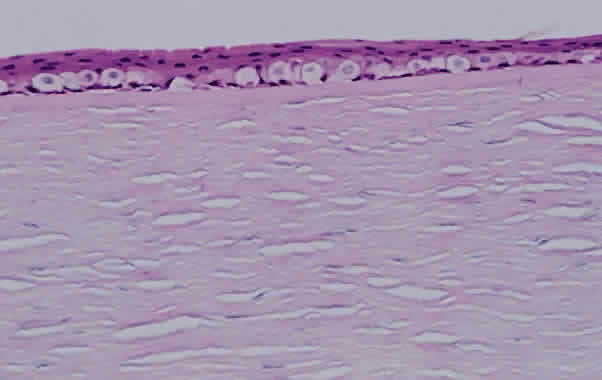

The corneal endothelium functions to maintain a state of relative dehydration of the corneal stroma, which permits the orderly arrangement of the stromal lamellae and, thus, transparency.150 Because the corneal endothelium does not regenerate, loss of endothelial cells results in the enlargement of adjacent endothelial cells to compensate. With continued damage and loss, these enlarged cells are unable to maintain the required degree of fluid transport and corneal edema results, eventually involving the entire stroma and finally the epithelium (Fig. 16).150 Edema of the corneal epithelium results in the failure of the hemidesmosomes between the basal epithelium and Bowman's membrane, with subsequent bullae formation. Bullae may rupture, and eventually a fibrovascular tissue grows to cover the defect, resulting in corneal scarring (Fig. 17).

Fig. 16. Corneal epithelium showing edema of the basal epithelial layer (hematoxylin and eosin; × 200).